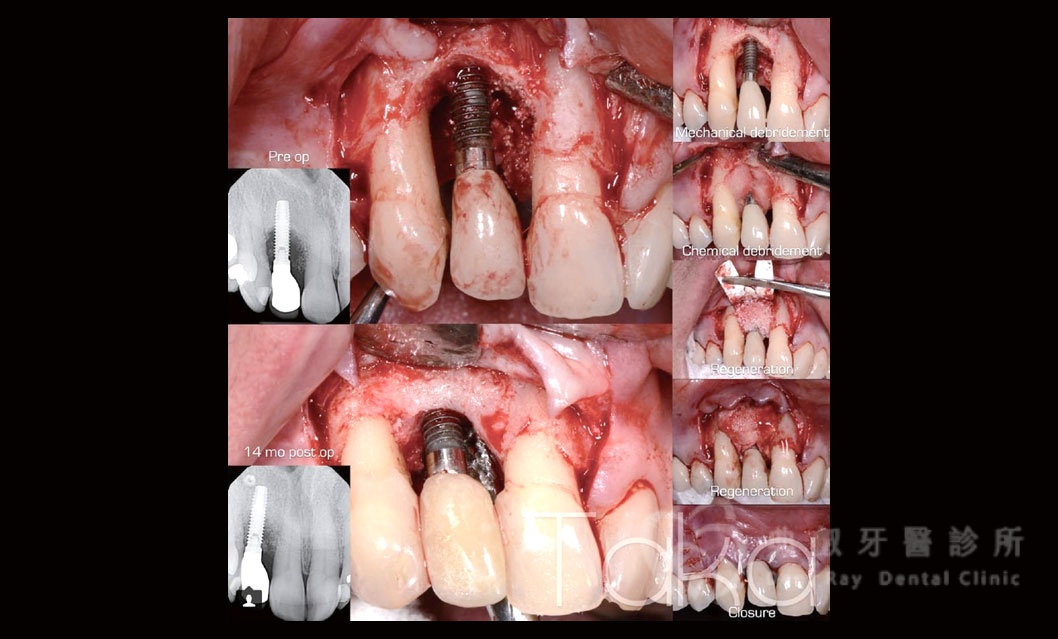

舊有植體失敗處理